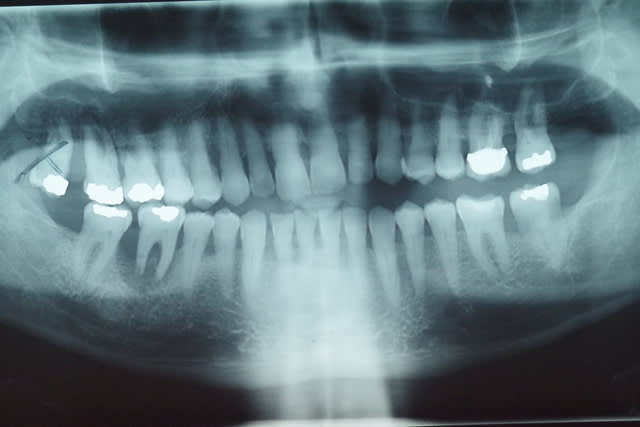

Le patient de 65 ans n'a plus d'occlusion sur le secteur ant et sur le secteur postérieur gauche.

L'occlusion ne se fait que sur les 5, 6 et 7 côté droit.

De ce fait la surcharge occlusale sur la 46 a entraîné une lyse osseuse importante qui contre indique la conservation de cette dent.

Cette lyse est sans doute aggravée par une hygiène très incertaine .

PS1 La ccm sur 26 a été réalisée en occlusion en 2005

J'entends par là que ce monsieur a l'ATM gauche luxée, probablement depuis un bout de temps. J'imagine que ça se verrait à la pano si les ATM étaient dans le cadre.

Concernant une radio des ATM, mon centre de radio m'a précisé que cela ne se faisait plus car la SS ne remboursait plus !!

Ils veulent faire une pano centré sur les ATM.

Je pense la faire faire afin d'éliminer définitivement une luxation de la mandibule.

Une pano montrant les ATM permettra de confirmer ou non la théorie de la luxation mandibulaire: plus de doutes possibles. L'IRM permettra d'écarter un autre problème ATM (luxation du disque), qui serait cependant bien étonnante au vu des symptômes.

Je pense aussi qu une pano bouche fermée et une en bouche ouverte serait intéressante pour savoir s il y a une luxation.

> Une pano montrant les ATM

SANS LA CALE INCISIVE : EN OCCLUSION!! ça te permettra de voir la place de tes condyles dans les cavités glénoïdes en occlusion. Si la luxation est permanente tu la verras.

Je vais faire faire au patient ces prochains jours une pano centrée sur les ATM bouche fermée.